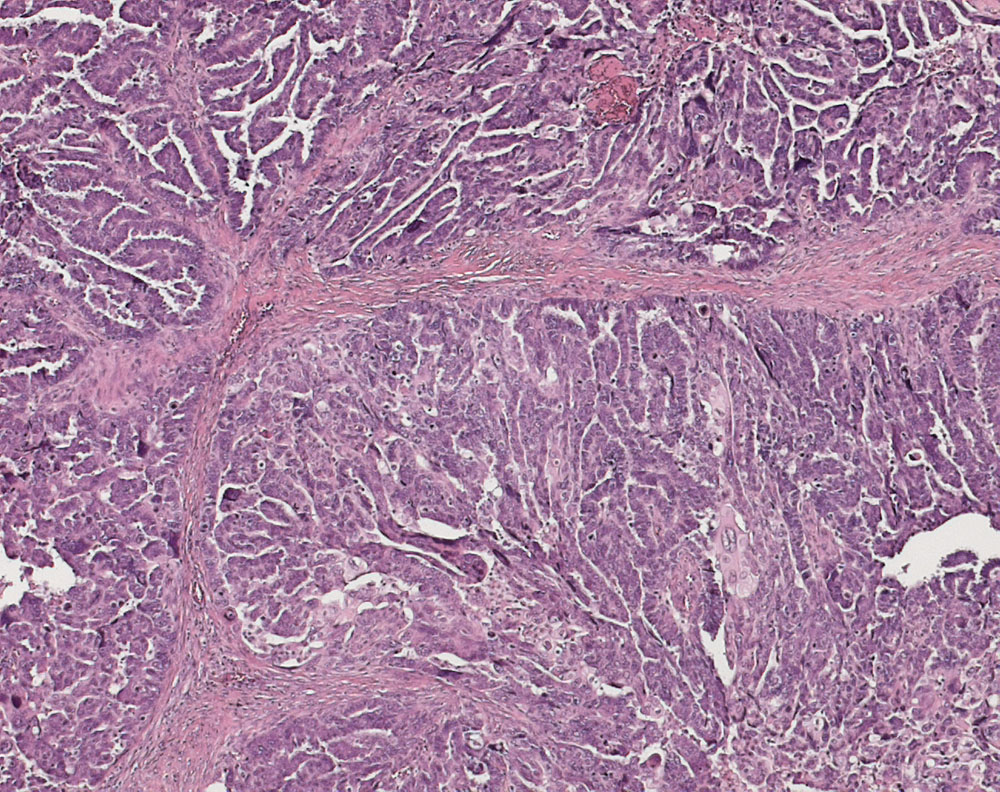

seröses Ovarialkarzinom high grade

Papillen und Drüsen mit schlitzförmigen Lumina.

Verdacht auf Ovarialkarzinom (CA125 > 2000u/l). CT: Vergrösserte Ovarian beidseits. Maligner Pleuraerguss Adenokarzinom.